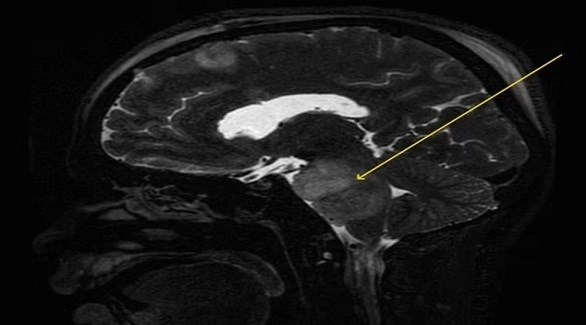

وسعى الرجل المجهول الهوية، وهو في أوائل الثلاثينيات من عمره، إلى الحصول على علاج طبي لصداع تسبب له بالألم لأكثر من أسبوعين، كما اشتكى من القيء ثلاث مرات في اليوم، بحسب تقرير حالة عن مرضه.وبدأت صحة الرجل في التدهور قبل أربعة أشهر، عندما بدأ يعاني من الفواق المتكرر، حتى أصبح الفواق في النهاية مستمراً، مما أثر على كل من أنماط نومه وتناوله للطعام، وتم إجراء فحوصات الدماغ للوصول إلى جوهر مرضه الغامض.وكشفت النتائج عن إصابة الرجل بورم دبقي جسري منتشر، وهو نوع شديد العدوانية ويصعب علاجه من أورام المخ، وبدأت الفواق لدى الرجل بالتوقف بعد بدء العلاج من السرطان. وافترض الخبراء أن الورم يؤثر على جزء من جذع الدماغ المسؤول عن التحكم في الأعصاب والعضلات التي تثير عادة استجابة الفواق.وقال الرجل إنه طلب من الأطباء المساعدة في علاج الفواق من قبل، ولكن دون جدوى، وبعد سلسلة من اختبارات الدم والفحص البدني، قرر المسعفون أن يخضع الرجل لفحص الأشعة المقطعية، ووجدوا آفة في دماغه، قبل أن يخضع لفحص تصوير بالرنين المغناطيسي أكثر تفصيلاً.وكشف تصوير بالرنين المغناطيسي عن كتلة من الأنسجة تدل على وجود ورم دبقي جسري، وهو نوع من ورم الدماغ ينمو على جذع الدماغ، وهو الجزء الذي يربط العضو بالعمود الفقري، بالإضافة إلى نزيف داخلي داخل الدماغ نفسه.ومن المستحيل إزالة الأورام الدبقية الجسرية جراحياً بسبب مدى ترابطها مع جذع الدماغ الفعلي، وتم إرسال الرجل لإجراء عملية جراحية، حيث قطع الجراحون دماغه لتخفيف الضغط داخل جمجمته، والذي نتج عن تراكم السوائل في الدماغ. وبعد ثمانية أيام من الشفاء، خضع الرجل لدورة علاج إشعاعي لمدة ستة أسابيع في محاولة لقتل الورم.وقال الدكتور ناجاسوبرامانيام فيمبالي، من معهد عموم الهند للعلوم الطبية "بدأ الفواق لدى المريض بالتلاشي بعد بدء العلاج الإشعاعي وبعد شهر واحد من العلاج الإشعاعي، هدأ الفواق بشكل كبير".وأضاف الدكتور فيمبالي أن الحالة أثبتت أهمية تحديد الأطباء لأسباب الفواق المستمر في الوقت المناسب لضمان عدم تعرض المريض لمزيد من المضاعفات، بحسب صحيفة ديلي ميل البريطانية.يعاني من الحازوقة 4 أشهر بسبب ورم في المخ